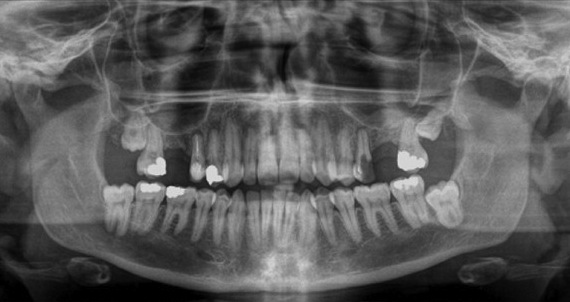

- оценить состояние зуба под пломбой, состояние каналов, верхушек корней;

- диагностировать скрытый кариес;

- диагностировать проблемы периодонта;

- увидеть ретенцию и наличие сверхкомплектных зубов;

- дает детальную информацию о расположении зубов «мудрости».

Благодаря такому снимку можно контролировать состояние при имплантации, протезировании, а также ортодонтическое лечение.

- Терапевтическая стоматология – помогает оценить качество пломбировки корневых каналов, расположение пломбы по отношению к пульпе зуба, наличие воспаления за пределами корней.

- Хирургическая стоматология – даёт представление о форме и количестве корней перед удалением зубов, перед удалением зубов мудрости (в том числе ретенированных), а также перед удалением кист зубов.

- Имплантология – начальное планирование имплантации до 3D КЛКТ снимка, контроль за приживлением имплантов и костного графта после выполнения синус-лифтинга.